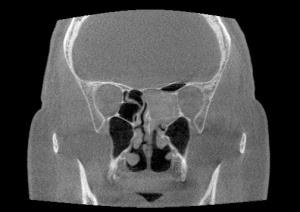

Computed tomography (CT) of the orbit is the initial imaging modality of choice for diagnosing and characterizing the extent of orbital aspergillosis, as it is quick and effective. Aspergillus appears as isodense, heterogenous lesions affecting the paranasal sinuses with calcification and bony erosion. The sphenoid sinus is the most commonly affected paranasal sinus, which is postulated to be related to its low oxygen content and acidic environment (Figures 1 and 2). The presence of patchy hyperattenuation is also considered an indirect indicator of fungal disease.[16] MRI reveals hypointense lesions on T1 and T2-weight images in contrast to neoplastic and bacterial lesions which are hypertense on T-2 weighted images.[8] MRI is generally preferred to CT in evaluating the orbital apex, cavernous sinus, and optic nerve changes.